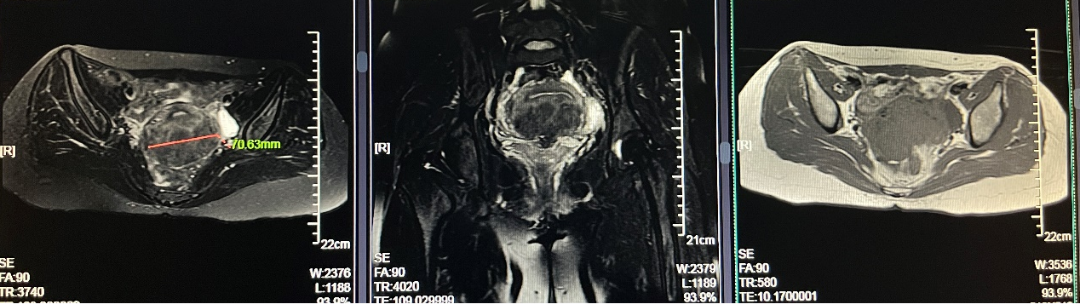

患者女,28岁,2021-06-07于青岛市妇女儿童医院就诊。 主诉:进行性痛经加重3年余。 现病史:患者月经初潮即有经期下腹痛,无需口服止痛药物。3年前痛经渐进性加重,目前经期腹痛VAS评分8分,伴恶心呕吐、肛周坠胀感。伴有非经期腹痛,VAS评分4分,持续4-5天,有深部性交痛。月经周期、经期及经量较前无明显改变。我院就诊超声提示:子宫后壁探及低回声结节,大小46mm*56mm*42mm,考虑子宫肌瘤。患者有明确生育要求,为求进一步治疗,门诊以“子宫腺肌病?子宫肌瘤?”收入院。患者自发病以来,神志清,精神可,饮食正常,经期夜间睡眠欠佳,体重较前无明显增减。 既往史:体健,否认慢性病及传染性疾病病史,否认外伤史,否认输血史,否认食物、药物过敏史。 月经及婚育史:既往月经规律,周期28-30天,经期5-6天,末次月经:2021-05-24。G1P0A1,2021年4月孕11周“稽留流产”行药物流产1次。 家族史:无特殊。 体格检查:T36.2℃,P77次/分,R18次/分,BP101/67mmHg,身高160cm,体重56kg。疼痛评分:0分。心、肺、腹部查体无异常。 专科查体: 妇科查体:外阴发育正常,阴道畅,宫颈光滑,子宫后位,增大如孕2月,固定、活动差,无压痛,双侧附件区未及异常。三合诊:左侧骶韧带触及触痛结节。 辅助检查: 2021-06-03 B超:子宫后位,宫体大小正常,形态规则,肌层内回声欠均匀,后壁肌层探及低回声结节,大小约46mm*56mm*42mm,边界清。宫腔内膜受压前移,厚10.1mm。宫颈形态正常。左侧卵巢探及液性暗区,大小约39mm*29mm,透声好,右侧卵巢大小正常。右侧附件区未见明显异常。 2021-06-07 肿瘤指标:糖类抗原CA19-9 52.21U/ml;糖类抗原CA125 112.9U/ml ↑; 2021-06-07 MRI提示:子宫后壁子宫腺肌病、盆腔子宫内膜异位症? 初步诊断: 2.盆腔子宫内膜异位症 3.不良孕产史 1.2021-06-08在镇静镇痛下行聚焦超声消融手术(FUAS)治疗。术后增强核磁检查提示子宫后壁腺肌病灶内无灌注区,子宫内膜及浆膜血流灌注正常。 2.2021-06-22术后第一次月经来潮,痛经较前减轻,VAS评分2-3分。术后辅助GnRh-a治疗3周期辅助治疗,同时口服钙片补钙治疗,用药期间闭经,无腹痛等不适。 3.GnRh-a治疗3周期后,2021-09-08复查B超:子宫后位,宫体大小正常,形态规则,肌层内回声欠均匀,后壁肌层探及高回声团,大小约38mm*37mm*26mm,边界清,内见少许血流信号。宫腔内膜受压前移,厚4.1mm。宫颈形态正常。双侧卵巢大小正常。双侧附件区未见明显异常。 4.2021-11-22月经复潮,经量正常,痛经VAS 2分,月经第5天开始口服地屈孕酮20mg QD,每月经周期20天,建议试孕半年。 5.2022-04-27随访复查,LMP:2022-02-24,停经9周,B超:子宫后位,体积增大,形态饱满,被膜光滑,后壁肌层回声不均匀,内见低回声区,较大范围约35mm*26mm,宫腔内见大小约32mm*31mm*24mm妊娠囊,张力可,内见胎芽,纵径22.4mm,心管搏动规律,妊娠囊下方探及不规则液性暗区,范围约21mm*8mm。双侧附件区未见明显异常。继续口服地屈孕酮10mg q8h保胎治疗。孕期进展顺利,2022-11-25外院足月剖宫产1女婴,体重3300g,Apgar评分10分-10分。 子宫内膜异位症和子宫腺肌病是妇科常见疾病。除了引起疼痛和月经改变,越来越多的证据表明,这两种疾病对女性的生殖功能有重要影响。临床可表现为不孕不育和流产等,尤其是早期流产[1]。 本例患者B超提示“子宫肌瘤”可能,但后续评估更符合子宫腺肌病。弥漫性子宫腺肌病的超声检查准确性较高,但子宫腺肌瘤超声表现与子宫肌瘤相似,临床诊断需要结合患者的症状、CA125水平综合判断。相比超声,磁共振检查对子宫腺肌病的分型更有优势,也更容易发现合并的盆腔子宫内膜异位症。后位子宫的后壁腺肌病灶往往合并子宫直肠陷凹的内异病灶,本例患者即属于该情况,治疗策略应兼顾两种疾病并同时考虑患者的生育需求。 针对子宫腺肌病,传统的病灶切除手术对子宫损伤较大,合并盆腔子宫内膜异位症时,手术操作也较困难,所以对于有生育需求的患者选择手术治疗需要相当慎重。聚焦超声消融术(HIFU)可选择性消融子宫腺肌病病灶、使病灶缩小,同时保护子宫完整性,从而达到减轻症状、缩小病灶、改善生育的目的[2]。但无法同时消融盆腔子宫内膜异位病灶,需要联合药物综合治疗。 子宫腺肌病和子宫内膜异位症的慢病管理理念已逐渐被认可,药物治疗是基石。而目前一线用药促性腺激素释放激素激动剂、地诺孕素等均会抑制排卵,有生育需求的患者备孕时需要停药。而停药后的试孕期病灶复发和进展风险较高,从而影响妊娠几率。地屈孕酮10-20mg/d可缓解内异症痛经,不抑制排卵,兼顾子宫腺肌病和盆腔子宫内膜异位症患者的治疗和备孕。此外,对于疑有黄体功能不足者黄体期使用地屈孕酮还可能提高自然受孕率,备孕期周期性用药副作用低,安全性高。 子宫腺肌病不仅可导致患者的生育力低下,诸如排卵障碍、不孕、流产、早产、死产、胎儿生长受限等,还可导致妊娠期母亲并发症如剖宫产率增加、子痫前期、前置胎盘及胎盘早剥等[3],一旦妊娠应更加积极的给予保胎治疗和严密随访,积极补充孕酮以抑制子宫平滑肌收缩,尽可能提高活产率。 子宫腺肌病和子宫内膜异位症具有类似的发病机制,也常常合并存在,严重影响女性的生殖健康。针对两种疾病的治疗应规范化、个体化、微创化。给予规范用药或手术治疗,减灭和消除病灶,减轻临床症状的同时,应充分考虑患者的主要诉求、年龄和生育需求,尽可能选取创伤小的治疗方式。重视患者全生命周期的管理,早诊早治、促进生育、长期管理预防复发,避免反复手术带来的创伤,定期随访,警惕恶变。 该患者28岁,痛经伴非经期腹痛,临床诊断符合子宫腺肌瘤合并子宫内膜异位症。既往不良孕产史,有明确生育需求,具有治疗指征。针对后壁子宫腺肌瘤传统手术方式对子宫损伤较大不利于患者后续妊娠,康医生选择了聚焦超声消融术治疗缩小子宫腺肌病病灶,减轻患者痛经并改善子宫形态,有利于提高妊娠几率。 子宫腺肌病和子宫内膜异位症在年轻患者中复发几率极高,可谓“不死的癌症”,当患者又有生育需求时,如何兼顾治疗和生育确实给我们提出了较高的要求。该患者在停用GnRh-a后月经来潮,备孕期间给予口服地屈孕酮稳定病灶、改善痛经,同时不会影响下丘脑-垂体-卵巢轴(HPO轴)而抑制排卵,还能提高自然受孕几率,可谓一举两得。 患者服用地屈孕酮3个月后便顺利妊娠,体现了治疗的有效性。更难能可贵的是,康医生重视子宫腺肌病患者的孕期管理,妊娠后继续给予口服地屈孕酮积极保胎,抑制子宫平滑肌收缩,也体现了将子宫腺肌病患者作为高危孕产妇管理的治疗理念。 参考文献: